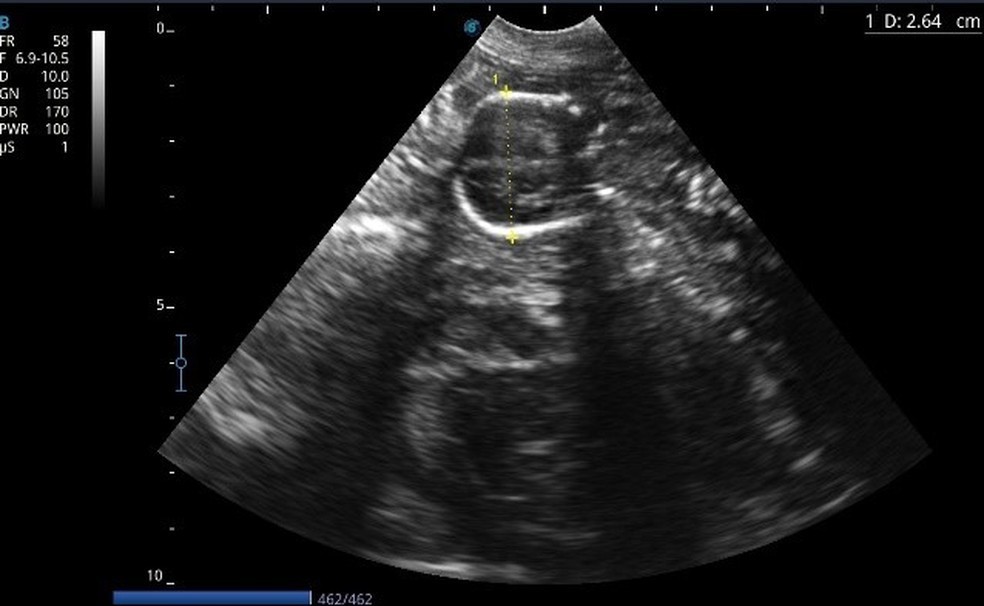

Ultrassom | Foto: Reprodução

Bruna contou que a dona, que pediu para não ser identificada e que também não permitiu a divulgação da imagem da cadela, relatou que a cachorra estava em trabalho de parto. A veterinária fez o encaminhamento para uma outra clínica para que fosse feito um exame de ultrassom.

Exame de ultrassom (foto: duvulgação)